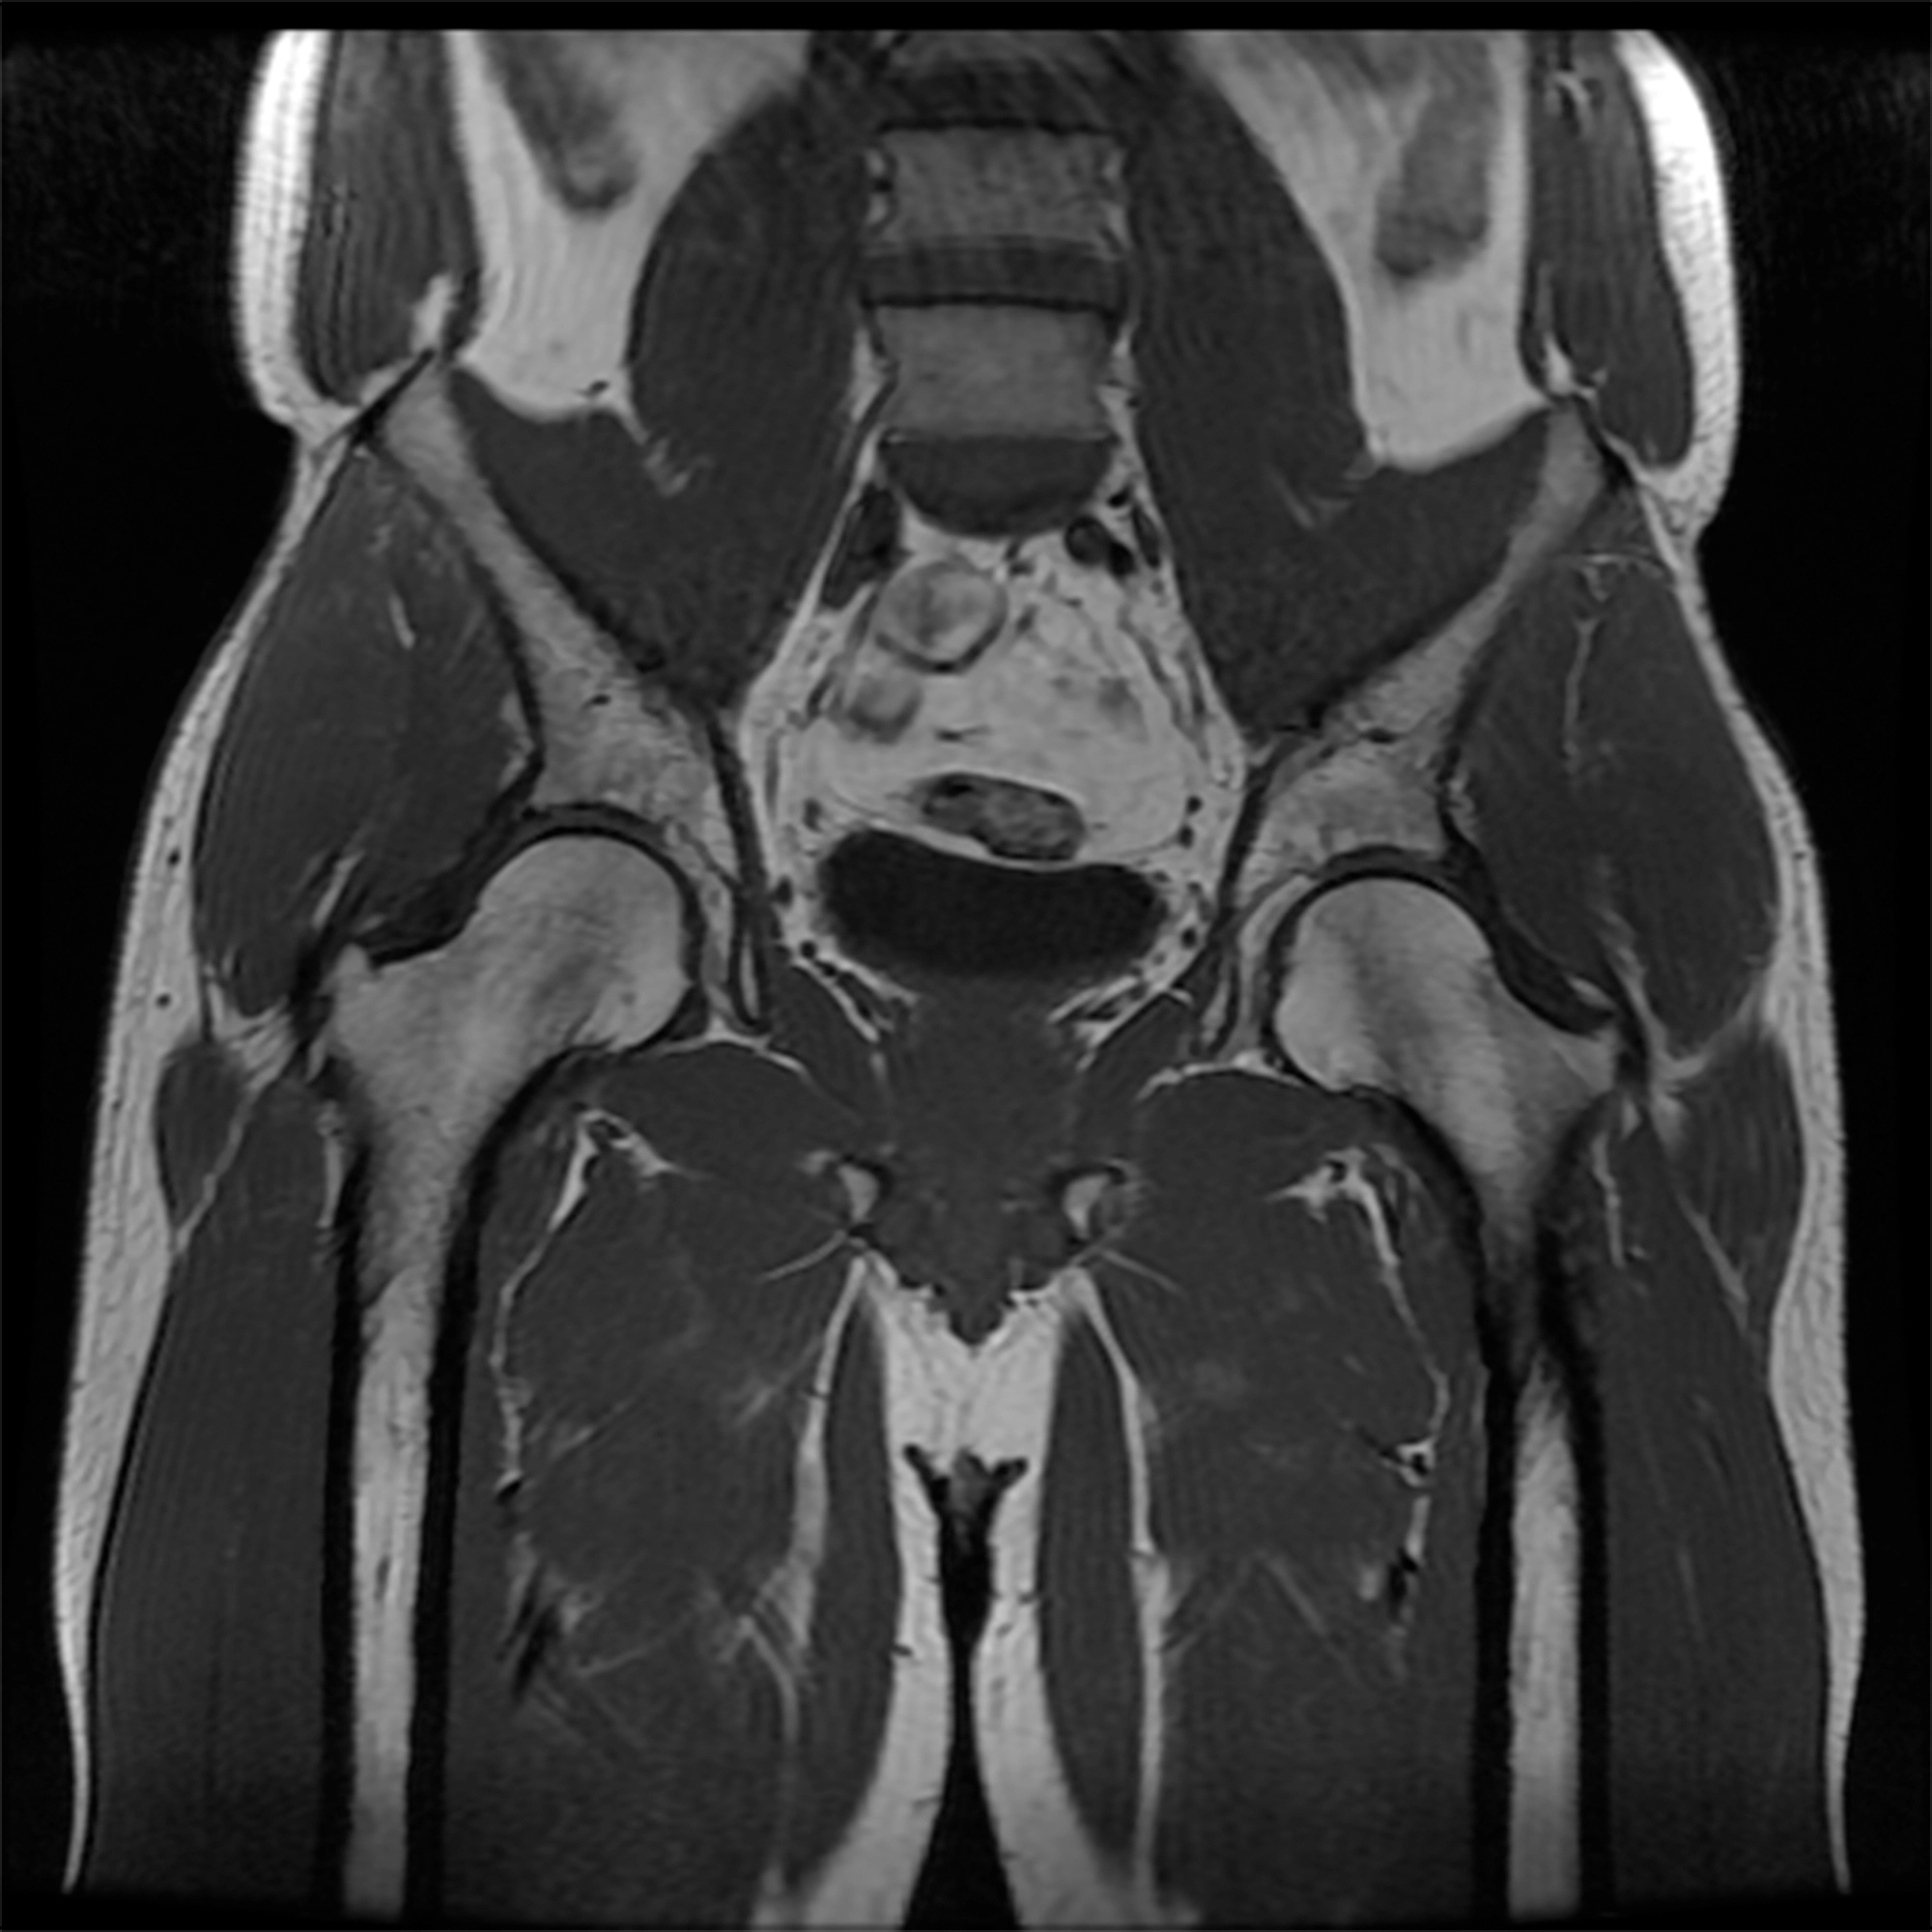

Continued pain after sacroiliac joint surgery

Marc Darrow, MD, JD. A doctor will diagnose failed sacroiliac (SI) joint fusion surgery after the patient continues to suffer from chronic pain and loss of function after the their procedure. There are many reasons why the surgery has failed. This includes pseudarthrosis (a non-union of the bones), The implants has loosened or caused fracture … Continue reading Continued pain after sacroiliac joint surgery